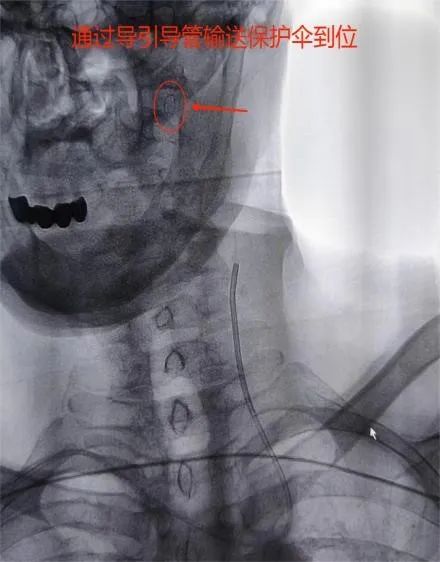

患者孙某因“急性脑梗死”来我院神经内三科就诊,完善相关检查发现该患左侧颈内动脉起始段重度狭窄。一旦闭塞将出现半身不遂等严重后果,为给予患者进一步治疗,以“颈动脉狭窄”收入我院神经内科三病区。因患者对常规股动脉穿刺入路存在恐惧心理,对导尿存在不适感,对股动脉穿刺可能产生的皮下血肿及假性动脉瘤等可能发生的并发症难以接受,经神经内三科医护团队的认真分析、研讨:1.患者右侧桡动脉搏动良好,符合穿刺置换的条件;2.Alle实验阴性;3.患者左侧颈总动脉发自头臂干,经桡动脉路径会更好到达责任血管。因此,决定由李士伟医生经右侧桡动脉入路行左侧颈动脉支架植入术。手术用时30分钟顺利完成,患者术后6小时即解除桡动脉压迫,自主 活动良好。